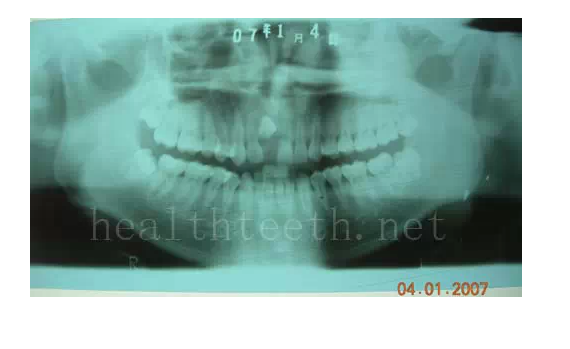

2、埋伏牙

其他埋伏牙

3、多生牙

病例1

病例2

病例3,同時多生兩顆牙齒